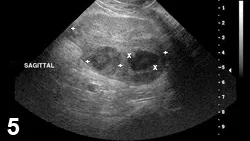

FIGURE 2

CBPH sagittal view (ventral is top of image, cranial is left) of a canine prostate with small anechoic parenchymal cysts.

• Characteristic appearance of BPH and CBPH on ultrasonography includes symmetric parenchymal striation with increased echogenicity and variable hypoechoic-to-anechoic intraparenchymal cystic structures (Figures 1 and 2).